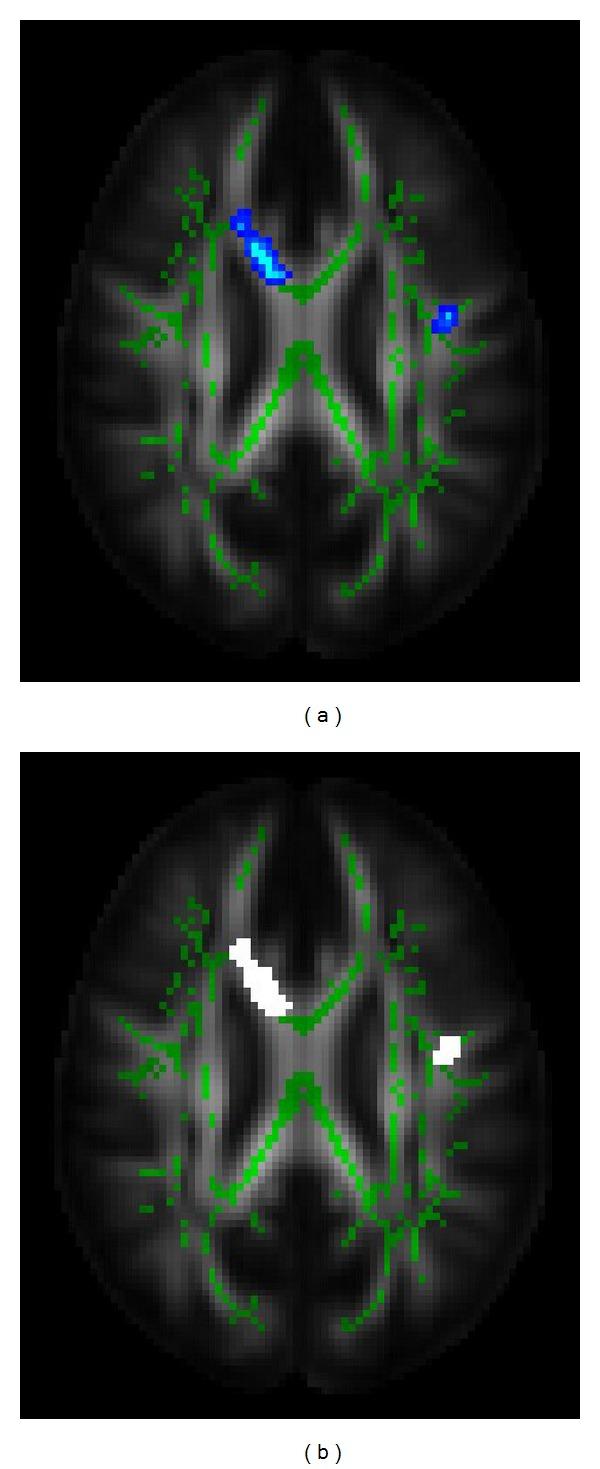

Stroke is a common neural disorder in neurology clinics. Magnetic resonance imaging (MRI) has become an important tool to assess the neural physiological changes under stroke, such as diffusion weighted imaging (DWI) and diffusion tensor imaging (DTI). Quantitative analysis of MRI images would help medical doctors to localize the stroke area in the diagnosis in terms of structural information and physiological characterization. However, current quantitative approaches can only provide localization of the disorder rather than measure physiological variation of subtypes of ischemic stroke. In the current study, we hypothesize that each kind of neural disorder would have its unique physiological characteristics, which could be reflected by DWI images on different gradients. Based on this hypothesis, a DWI-based neural fingerprinting technology was proposed to classify subtypes of ischemic stroke. The neural fingerprint was constructed by the signal intensity of the region of interest (ROI) on the DWI images under different gradients. The fingerprint derived from the manually drawn ROI could classify the subtypes with accuracy 100%. However, the classification accuracy was worse when using semiautomatic and automatic method in ROI segmentation. The preliminary results showed promising potential of DWI-based neural fingerprinting technology in stroke subtype classification. Further studies will be carried out for enhancing the fingerprinting accuracy and its application in other clinical practices.

中风是神经科门诊常见的神经疾病。磁共振成像(MRI)已成为评估中风情况下神经生理变化的重要工具,如扩散加权成像(DWI)和扩散张量成像(DTI)。MRI图像的定量分析有助于医生根据结构信息和生理特征在诊断中定位中风区域。然而,目前的定量方法只能提供疾病的定位,而无法测量缺血性中风亚型的生理变化。在本研究中,我们假设每种神经疾病都有其独特的生理特征,这可以通过不同梯度的DWI图像反映出来。基于这一假设,提出了一种基于DWI的神经指纹技术来对缺血性中风亚型进行分类。神经指纹由不同梯度下DWI图像上感兴趣区域(ROI)的信号强度构建而成。从手动绘制的ROI得出的指纹能够以100%的准确率对亚型进行分类。然而,在ROI分割中使用半自动和自动方法时,分类准确率较低。初步结果显示基于DWI的神经指纹技术在中风亚型分类中具有广阔的应用前景。将开展进一步研究以提高指纹识别准确率及其在其他临床实践中的应用。